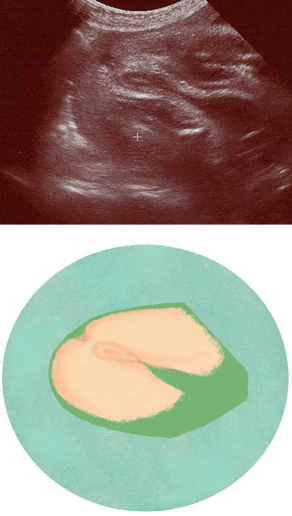

妊娠31週ころの超音波写真

おしり側から外性器の形がわかることもあります

女の子の外性器は、おしり側から見たときにわかることが多いでしょう。女の子の外性器は比較的28~33週ごろに見えやすく、男の子の外性器は、臨月まで見えることがあります。